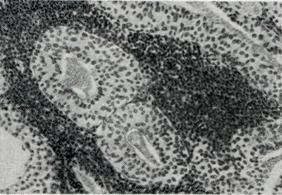

АденолимфомаАденолимфома (adenolymphoma; греческое aden — железа + лимфома; синонимы: лимфоматозная папиллярная цистаденома, бранхиома, бранхиогенная аденома, орбитальная инклюзионная киста, опухоль Уортина) — доброкачественная опухоль слюнных желез. Макроскопически аденолимфома представляет собой округлый или дольчатый узел не более 8 сантиметров в диаметре, мягкой консистенции, иногда содержащий кисты и обычно полностью инкапсулированный. Микроскопически (рис. 1.) аденолимфома состоит из трубчатых желез с нитевидными или широкими сосочками, выстланными высоким светлым цилиндрическим эпителием. В строме опухоли расположены многочисленные лимфоциты, формирующие фолликулы с центрами размножения. Лимфоидный компонент не является опухолевым ингредиентом, и поэтому термин «аденолимфома» не вполне правомерен. Аденолимфома возникает в любом возрасте, но обычно развивается у мужчин после 40 лет и составляет около 6% всех эпителиальных опухолей слюнных желез. Чаще аденолимфома располагается в области нижнего полюса околоушной слюнной железы, в ее толще или непосредственно у наружной границы органа. Нередко поражение бывает двусторонним или в виде множественных изолированных узелков. Аденолимфома может возникать в слюнных железах другой локализации или слезной железе.